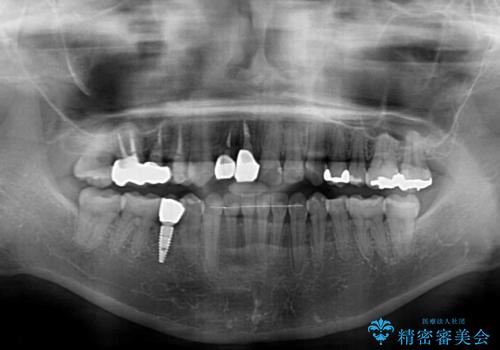

- 前歯が痛いとのことで来院された患者様です。

前歯は根管治療が必要であったため、まずは根管治療を行いましたが、痛みが引いた後、矯正治療や前々から治療が必要と言われてきた歯を治療したいとのことでした。

前歯のクロスバイトはインビザラインで改善し、抜歯が必要な部分はインプラントを、その他むし歯が進行している歯はセラミッククラウンによる補綴治療することとしました。